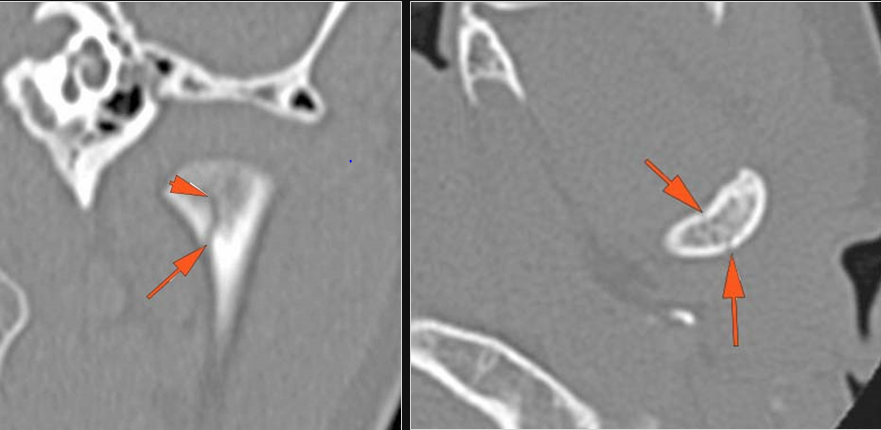

There is condylar fracture either within or outside of the joint capsule, or with or without involvement of the articular surface of the condylar head.

There is evidence of radiodense intra-articular osteochondral fragments.

There is bony injury or displacement of the external auditory canal and/or other evidence of temporal bone injury.